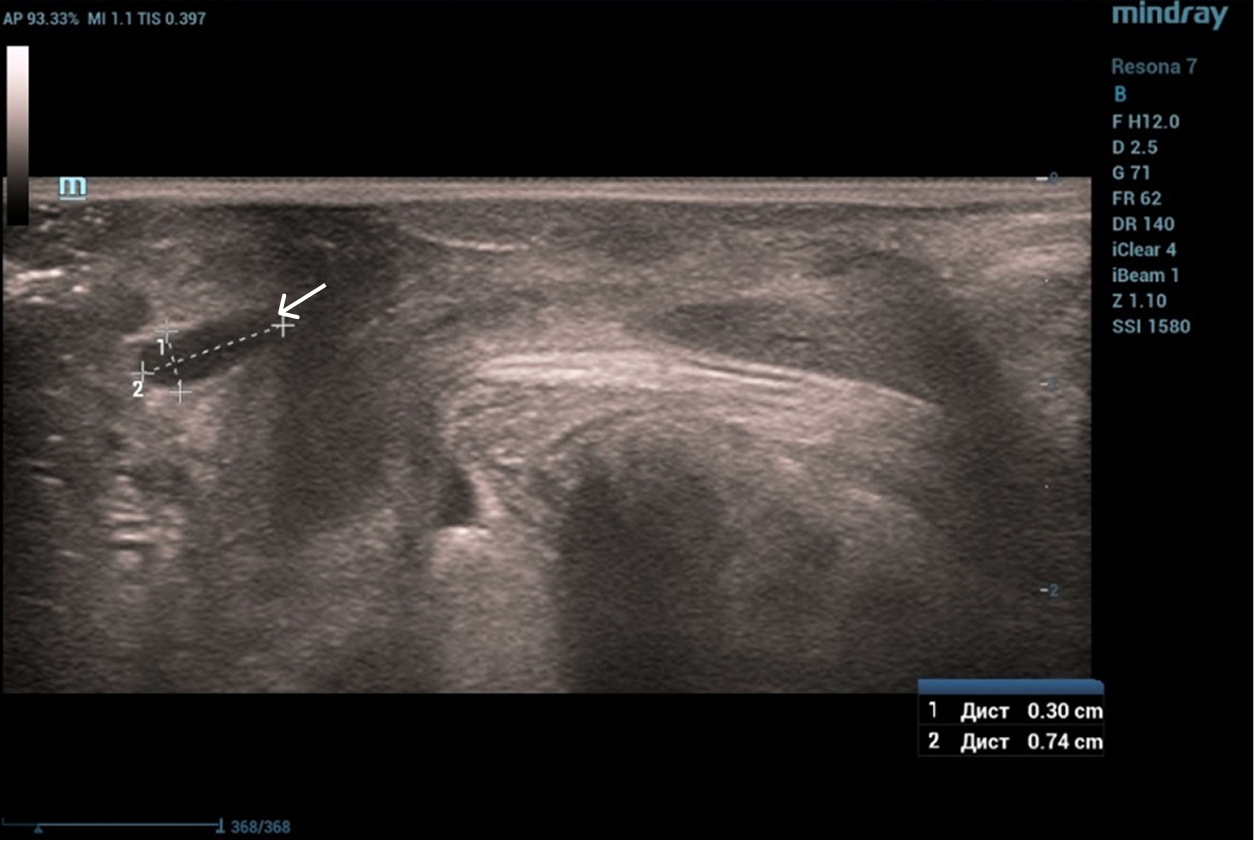

Трансперинеальный доступ, линейный датчик.

Слева от уретры округлое образование с четкой капсулой и мелкодисперсной взвесью размерами 1,5×1,0 см (филлер с воспалением), справа — анэхогенное овоидное образование (филлер).

Эхограмма 1